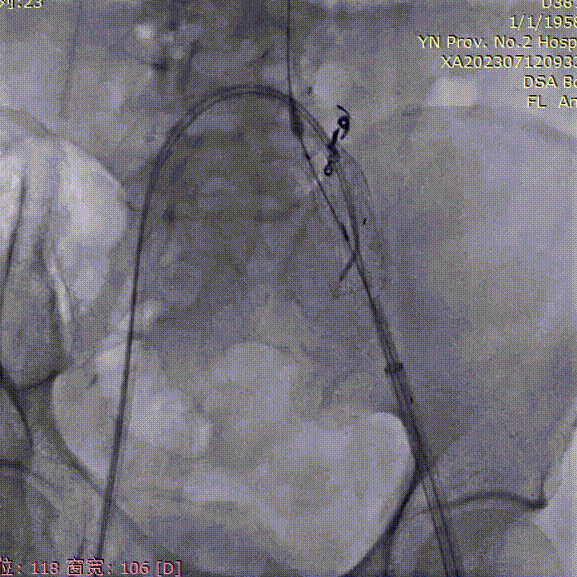

支架植入前造影

双侧股动脉入路,左侧置入18Fr 33cm GORE® DrySeal 亲水涂层导引鞘(以下简称“DSF导引鞘”),右侧置入12Fr 45cm DSF导引鞘;建立翻山通路后将标记猪尾导管头端置于肾动脉开口上方,做腹主动脉造影:显影显示双侧髂总动脉瘤;肾动脉开口到右髂内距离约200mm。